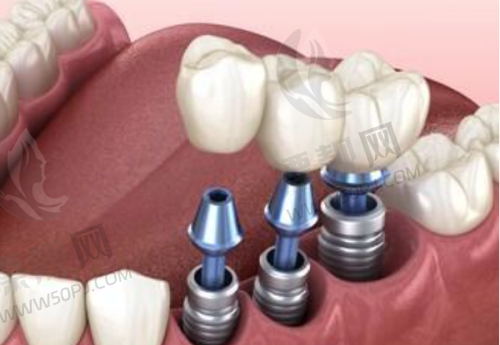

1)数字化种植牙技术:采用德国卡瓦(Kavo)设备,3D影像辅助下进行数字引导种植,听起来就高大上。